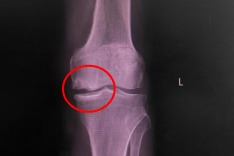

▲膝关节单髁置换术前术后 保留健康组织的治疗理念 膝关节单髁置换术通过微创技术仅置换病变严重的单侧间室(内侧或外侧),这种“精准定位”的治疗方式,能够尽可能保留患者健康的骨组织、韧带及本体感觉,手术创伤相对较小。术后患者疼痛可得到缓解,膝关节的自然活动功能得以保留,步态恢复更趋向自然协调。 多学科协作优化恢复流程 快速康复外科理念贯穿于治疗全程,为患者提供标准化、个性化的康复路径。术前进行全面评估和健康宣教,帮助患者做好身心准备;术中采用精细化操作,减少组织损伤;术后早期康复师介入指导功能锻炼。这种多学科协作模式有助于缩短住院时间,多数患者能在短期内达到出院标准,更快回归家庭生活。 护理团队实施全程化健康管理,从入院到出院后随访,提供涵盖疾病知识、康复锻炼、居家护理等全方位指导。针对患者术后可能出现的心理压力,医护人员可提供专业心理疏导,帮助建立积极康复的信心。 个性化方案助力功能恢复 膝关节功能的良好恢复,离不开科学系统的康复训练。专业医疗团队会为患者量身定制康复计划:早期进行关节活动度训练,防止粘连;中期强化肌力训练,增强关节稳定性;后期优化步态训练,提升活动协调性。通过循序渐进的康复锻炼,多数患者能够恢复日常活动能力,完成行走、上下楼梯等动作。 微创技术的临床应用优势 膝关节单髁置换术的临床应用特点包括:手术切口较小,术后疼痛轻,恢复时间短;保留更多自身组织,关节活动更接近自然状态;术后并发症风险低,康复效果稳定。临床实践中,患者在疼痛缓解、关节功能恢复及生活质量改善等方面可获得良好反馈。 健康提醒 当膝关节疼痛严重影响生活质量时,及时寻求专业医疗帮助至关重要。通过精准微创技术、快速康复流程和个性化护理方案,膝关节单髁置换术为患者提供了一种重获行动自由的可能。科学应对膝关节炎,才能让生活回归轻盈与活力。 关节骨病科简介 基本概况 我院关节骨病科现开放床位32张,汇聚了16名经验丰富、技术精湛的专业医护人员。科室以关节疾病诊疗、运动医学修复、骨病外科治疗为核心发展方向,深耕骨关节疾病、运动损伤、病理性骨折及骨科肿瘤等领域,为患者提供全方位、个性化的精准医疗服务。 诊疗技术 关节置换与翻修:早期股骨头坏死保髋术,人工股骨头/全髋关节置换术,髋关节翻修术,膝关节单髁置换/表面置换术,膝关节翻修术,人工肩关节置换术。 关节镜微创技术:关节镜下膝关节前后交叉韧带重建术,半月板缝合/成形术,关节内骨折镜下复位内固定术,肩袖修复术,肩关节不稳修复术,肩峰成形术,踝关节镜下韧带修复重建术。 骨肿瘤综合治疗:四肢骨肿瘤切除重建(含关节置换),骨肿瘤保肢术、化疗术。 其他骨病治疗:骨结核病灶清除植骨术,同种异体骨移植,各类病灶清除术,肢体矫形修复术。 专家简介 周仁实 主任医师、副院长。 1996广东医科大学临床医学本科毕业,从事骨科临床工作20多年。发表SCI论文1篇(通信作者),国家级省级论文10多篇。社会兼职:广东省医学教育委员会脊柱专业委员会副主任委员,广东省医师协会理事等。 擅长领域:擅长脊柱内固定、脊柱微创、骨肿瘤、关节置换、关节镜等技术,熟悉掌握骨科常见病与多发病的诊断与治疗。 欧阳思强 骨外科主任医师,关节骨病科主任。 广东省医师协会骨关节外科医师分会委员。2003年毕业于广东医学院临床医学系,毕业后一直从事骨科工作,曾先后到南方医科大学附属南方医院、广东省中医院进修。 擅长领域:擅长关节、骨病,运动损伤等疾病的诊断治疗;熟练掌握人工关节置换、人工关节翻修、骨关节病治疗,以及运动损伤疾病的关节镜下手术治疗等。 李远志 中西医结合医学副主任医师,关节骨病科副主任,硕士研究生学历。 2009年毕业于福建中医药大学,曾先后到河南省洛阳正骨医院、广州中医药大学一附院骨关节病科进修学习。 擅长领域:擅长关节、脊柱、骨病等中西医结合治疗。 黄平 骨外科主任医师。 曾到广州南方医学院创伤骨科进修学习。 擅长领域:擅长骨关节病、骨肿瘤的诊治;熟练掌握各类长骨骨折手法复位及切开复位内固定治疗术,骨盆骨折切开复位内固定术、断肢再植术、各类创面修复术;能主刀完成人工全髋关节置换、人工膝关节表面置换手术,掌握了髋关节、膝关节翻修技术。 苏中南 骨科主治医师。 2012年毕业于三峡大学临床医学系。曾到暨南大学附属第一医院进修学习关节、运动医学专业。 擅长领域:熟悉人工关节置换、关节镜的检查和治疗,擅长关节、骨病、运动损伤、脊柱等常见病与多发病的诊断与治疗。 王德信 中医骨伤主治医师,研究生学历。 擅长领域:熟练掌握四肢骨折正骨、运动创伤、大面积烧伤、慢性溃疡创面修复处理、关节脱位整复,四肢骨关节疾病诊治。熟悉应用内固定及外固定技术治疗各种常见骨折,能运用中西医结合、辩证运用方剂保守治疗股骨颈骨折、股骨头缺血性坏死、风湿、类风湿关节炎、髋膝关节骨关节病、老年性骨质疏松等关节骨病科常见疾病。